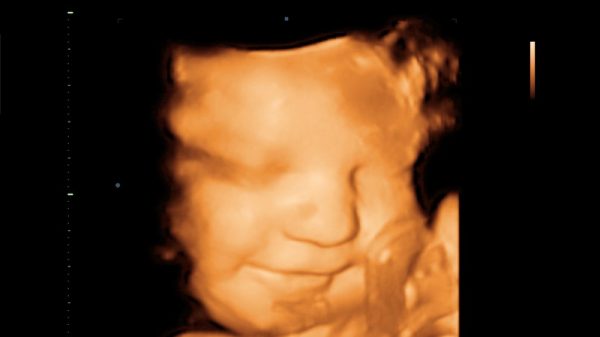

El lema elegido por la Marcha por la Vida 2019 no es casualidad: la alianza entre ciencia y mensaje pro vida es quizás uno de los rasgos más claros de la evolución en este terreno durante últimos años. Los avances en investigación y tecnología neonatal están cambiando muchos de los términos del debate. El uso de técnicas de ultrasonido nos permite ahora ver con un detalle inimaginable hace unas décadas el desarrollo del niño por nacer. Ya no estamos hablando de conceptos abstractos, sino sobre el derecho a la vida de alguien que podemos ver chupándose el dedo, sonriendo o dando palmadas, alguien que ya no podemos descartar como no-humano. Tim Goeglein, vicepresidente de Focus on the Familiy, explicaba recientemente que estiman que 400.000 madres en Estados Unidos que se planteaban abortar han decidido continuar con su embarazo tras ver a sus hijos gracias al programa que ofrece máquinas de ultrasonidos a las clínicas. Por otra parte, la capacidad de supervivencia de un niño prematuro también ha cambiado sustancialmente gracias a los avances técnicos: si en 1973 era inviable que un feto de 28 semanas fuera viable, ahora se habla incluso de viabilidad a partir de las 22 semanas, como incluso recogía el New York Times, un diario alineado con las tesis abortistas.